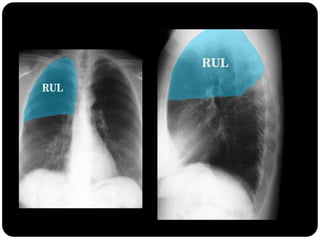

Atelectasia

 Diminuição de volume do segmento, deslocamento de uma ou mais

fissuras interlobares em direção à parte atelectasiada, desvio do mediastino

para o lado envolvido, deslocamento hilar, estreitamento dos espaços

intercostais e hiperinsuflação dos outros lobos / segmentos não atelectasiados

de forma compensatória.

Ex: Colapso do

LSD

Observar

deslocamento de

fissura!

Atelectasia do lobo

superior direito

Atelectasia do Lobo Sup. D.